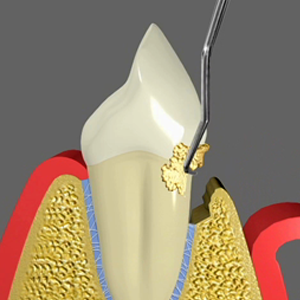

Scaling

Scaling is one of the most important processes in periodontal care which helps in curing gum diseases. The procedure involves removal of tarter from the tooth surface and roots. Periodontists use special instruments to clean the surface of the teeth. The instruments clean the gum pockets and reach the teeth roots to remove hardened tarter. Local anaesthesia may be used during the process to relieve patients from pain. The periodontist guides patients about routine maintenance and they may have to visit the dental practice frequently in order to keep the periodontal disease in control.